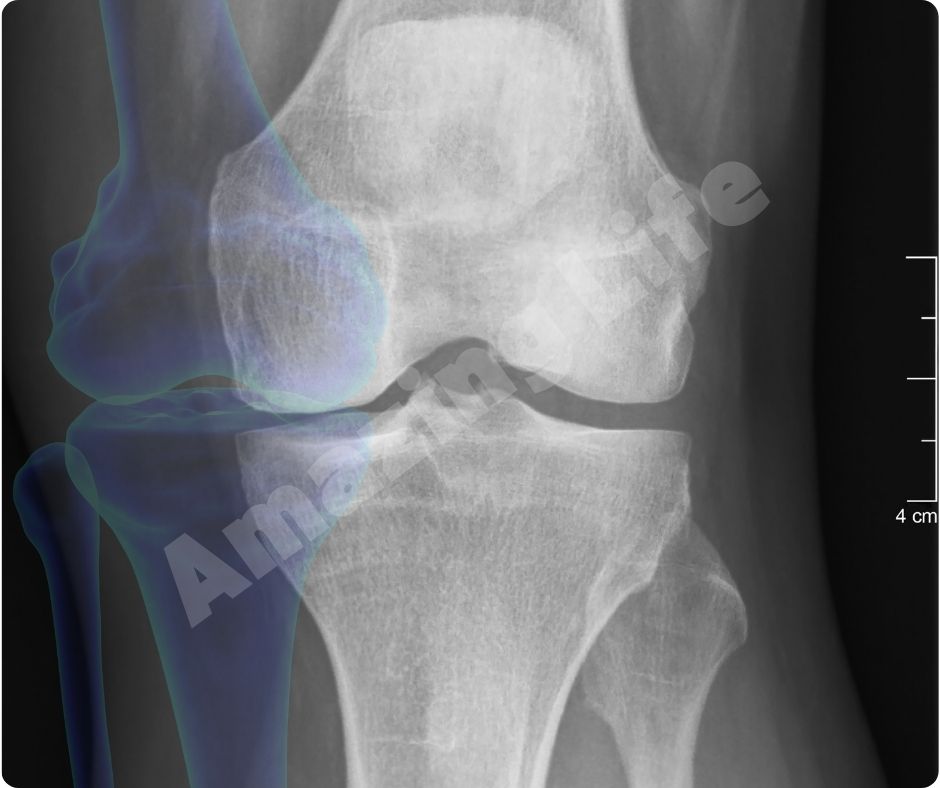

콘드로이친 효능은 특히 골관절염 환자들에게 효과적입니다. 여러 연구에 따르면, 콘드로이친이 연골의 분해를 억제하고, 연골을 보호하며, 통증을 줄이는 데 도움을 준다고 합니다. 2023년의 한 연구에서는 콘드로이친과 글루코사민을 함께 섭취하면 무릎 관절염의 진행을 늦출 수 있다고 보고했습니다.